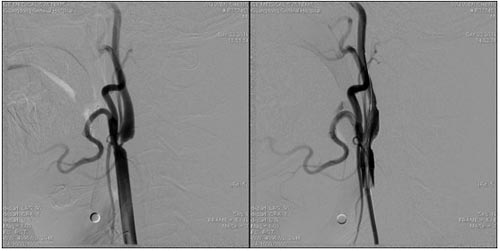

颈内动脉海绵窦漏(CCF)栓塞术前 颈内动脉海绵窦漏(CCF)栓塞术后